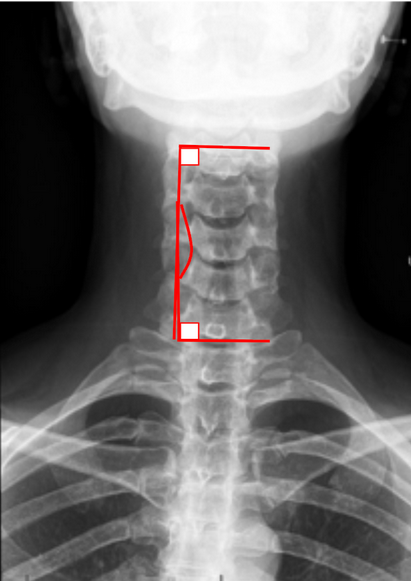

C2-C7 Coronal Cobb Angle

The C2–C7 Coronal Cobb Angle quantifies coronal (frontal plane) alignment of the cervical spine. It is used to assess cervical scoliosis or lateral deviation of the cervical spine from the vertical axis.

This measurement provides a standardized method to evaluate deformity severity and progression, particularly in cases of congenital scoliosis, degenerative changes, trauma, or postsurgical malalignment.

It is analogous to the Cobb angle used in thoracolumbar scoliosis evaluation but applied to the cervical region (C2–C7).

• Identify the superior endplate of C2 and the inferior endplate of C7.

• Draw a straight line along the superior endplate of C2.

• Draw another line along the inferior endplate of C7.

• Construct perpendicular lines from each of these endplate lines.

• The angle formed at the intersection of these perpendiculars is the C2–C7 Coronal Cobb Angle.

• The angle opens toward the convexity of the deformity.

• If the cervical spine deviates toward the right, it is a right-convex curve, and vice versa.